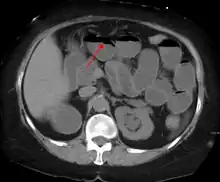

Causes of bowel obstruction include adhesions, hernias, volvulus, endometriosis, inflammatory bowel disease, appendicitis, tumors, diverticulitis, ischemic bowel, tuberculosis and intussusception.[1][2] Small bowel obstructions are most often due to adhesions and hernias while large bowel obstructions are most often due to tumors and volvulus.[1][2] The diagnosis may be made on plain X-rays; however, CT scan is more accurate.[1] Ultrasound or MRI may help in the diagnosis of children or pregnant women.[1]

The main diagnostic tools are blood tests, X-rays of the abdomen, CT scanning, and ultrasound. If a mass is identified, biopsy may determine the nature of the mass.

Radiological signs of bowel obstruction include bowel distension and the presence of multiple (more than six) gas-fluid levels on supine and erect abdominal radiographs. Ultrasounds may be as useful as CT scanning to make the diagnosis.[17]

Contrast enema or small bowel series or CT scan can be used to define the level of obstruction, whether the obstruction is partial or complete, and to help define the cause of the obstruction. The appearance of water-soluble contrast in the cecum on an abdominal radiograph within 24 hours of it being given by mouth predicts resolution of an adhesive small bowel obstruction with sensitivity of 97% and specificity of 96%.[18]